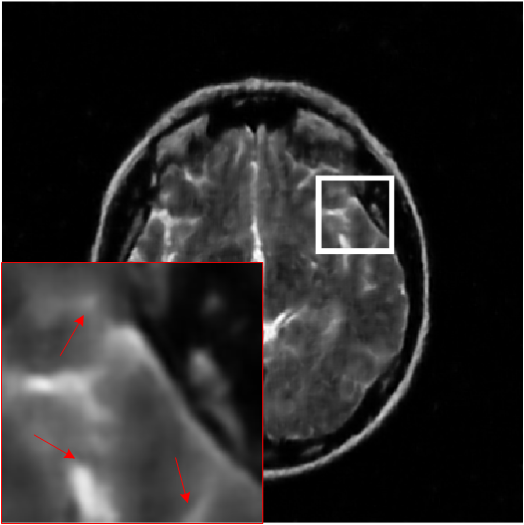

Figure 10: The reconstruction results on complex-valued MRI data. (a)-(c) are the PSNR values of different methods with three sampling masks and five sampling rates, in which the x-axis represents sampling rates. (d) is the standard deviation of PSNR values on different methods when using 30% sampling rates, in which the x-axis represents sampling masks. And (e)-(j) are the errors of six CSMRI methods.

We evaluate the performance of the proposed model using PSNR on complex-valued data and compare with two optimization-based methods and three deep-learning methods. We present the PSNR results for all sampling masks and five rates in Figs. 10(a)-(c) and it is obvious that the proposed model outperforms other five methods, which can demonstrate the effectiveness of MDN model on complex-valued data. Additionally, we provide the standard deviation on 80 test images of different methods when using 30% sampling rates of three masks in Fig. 10(d). We can observe that deep-learning methods obtain more stable performance than DLMRI and Sparse MRI. In Figs. 10(e)-(j), we show the absolute value of residuals of different algorithms using 30% radial sampling rate. We can see that the proposed model has less noise-like errors than other five methods.